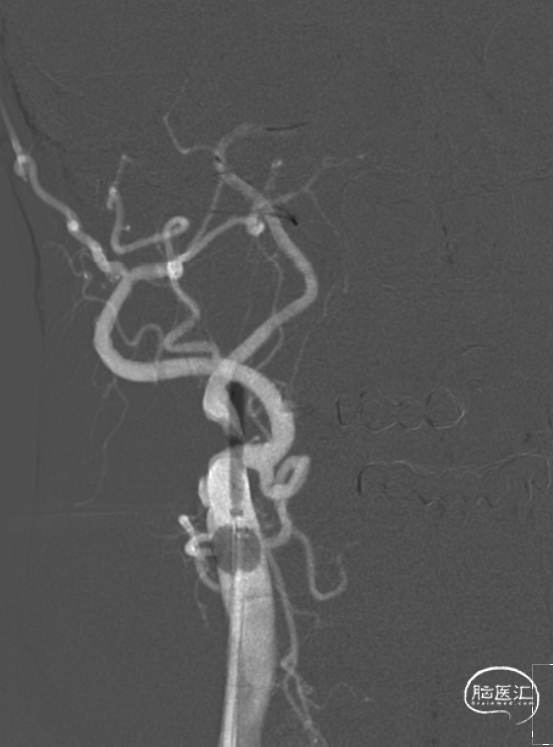

经泥鳅导丝引导,将通桥大禹™球囊导引导管送达右侧颈总动脉远端。路图下,将0.014*200cm微导丝通过狭窄段送达右侧颈内动脉C3段,将2.0*20mm球囊送达右侧颈内动脉狭窄段,给予6atm压力缓慢预扩张。

将保护伞送达右侧颈内动脉C2段,开伞,将3.0*20mm球囊送达右侧颈内动脉狭窄段。

充盈球囊导引导管阻断血流,给予7atm压力扩张回撤球囊,负压回抽球囊导引导管未见栓子吸出,释放球囊导引导管球囊。

将9*40mm 颈动脉支架送达目标区域,冒烟确认释放位置满意,释放支架。常规造影,血管成型满意,残余狭窄不足40%,前向血流mTICI 3级,远端血管未见缺如,收伞,伞内未见血栓。醒麻后病人清醒,安返病房。